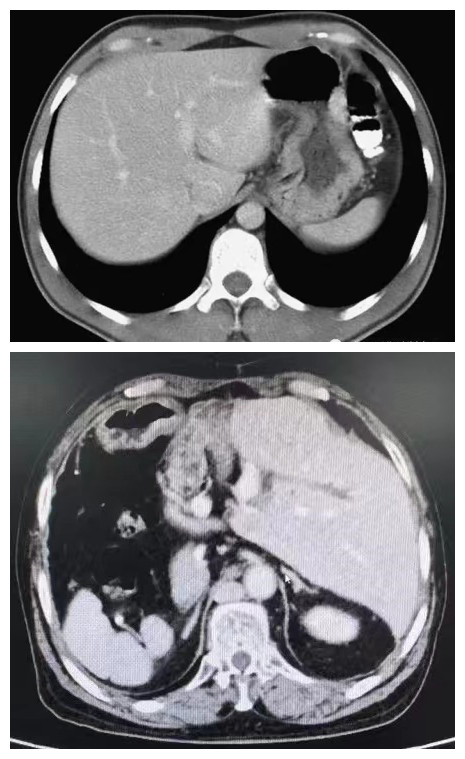

与正常人(上图)相比,颜女士的腹部CT显示器官相反

2024年元旦,本应欢度佳节颜女士因持续腹痛,眼黄、尿黄到捷克论坛 就诊,CT显示为胆总管结石,需手术治疗。但接诊的医生发现,颜女士五脏六腑“反着长”——肝、脾、胆等脏器的位置及血管走向与正常人完全相反,与正常人呈“镜面像”,是发生率为百万分之一的 “镜面人”。全内脏反位患者本身就极为罕见,而同时合并胆道疾病就更是少见。同时,颜女士曾因胆管癌、胆管结石及胆囊结石手术切除了部分左肝、胆管和胆囊,胆道的解剖学结构发生了很大改变,胃腔走形反位,左肝胆管走形、弯曲、变异,胆道呈“反Z字型”,这让颜女士的取石手术难上加难。